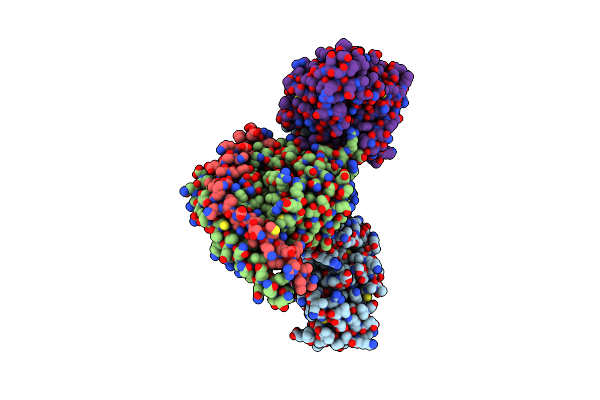

Cryo-Em Structure Of Ligand Histamine-Bound Histamine H4 Receptor Gi Complex

Organism: Homo sapiens

Method: ELECTRON MICROSCOPY Release Date: 2023-12-20 Classification: MEMBRANE PROTEIN Ligands: HSM |